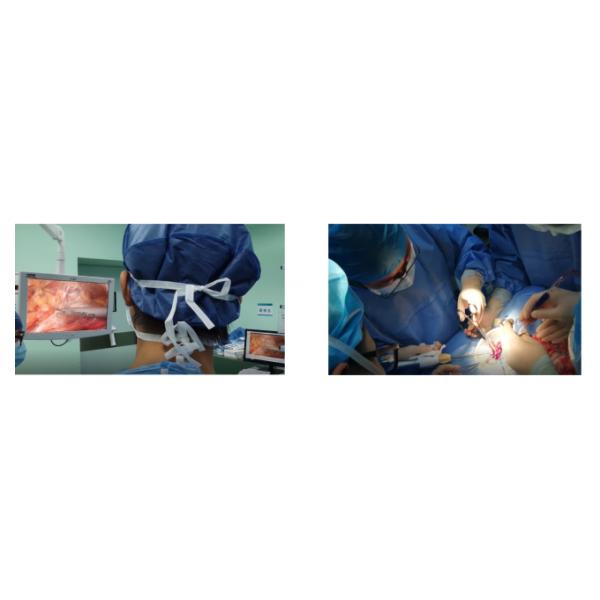

The endoscopic ultrasonic shear is a surgical instrument for hemostatic cutting and coagulation of soft tissue using. It uses mechanical energy

instead of electric current to cut and cauterize tissue. It works together with generator , handpiece, and/or footswitch.

It's mainly used in different surgeries:

(1) Ophthalmology and otorhinolaryngology: tonsillectomy, parotidectomy

(2) Head and neck surgery: thyroidectomy, cervical lymphadenectomy

(3) Breast surgery: radical mastectomy for breast cancer, mastectomy for breast lumps, axillary lymphatic dissection

(4) Hepatobiliary surgery: gallbladder and appendix surgery, liver surgery

(5) Thoracic surgery: radical surgery for esophageal cancer, radical surgery for lung cancer, mediastinal surgery

(6) Gastrointestinal surgery: gastric cancer, colorectal, pancreaticoduodenal surgery, hemorrhoid surgery

(7) Gynecology: adnexal resection, total hysterectomy, pelvic lymph node dissection

(8) Urology: minimally invasive surgery, renal cystectomy, adrenalectomy, radical cystectomy